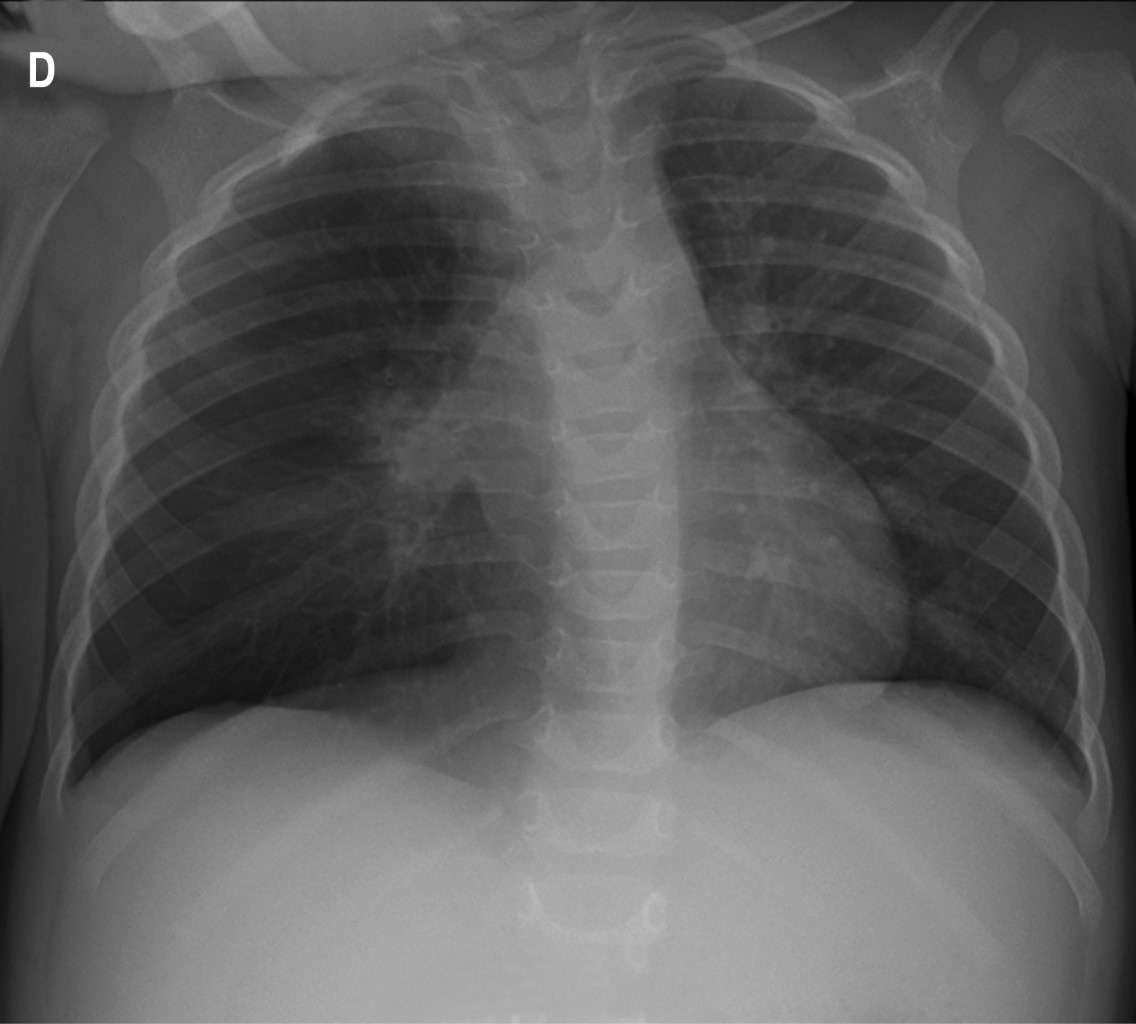

We present the radiological image of a 14-month-old infant who required hospital admission for acute bronchitis. Due to the persistence of the symptoms and asymmetry in the pulmonary auscultation, a chest X-ray was taken, in which hyperinflation of the right lung and partial atelectasis of the middle lobe were observed. These findings suggested aspiration of a foreign body, which was verified when the patient expelled it spontaneously, and the symptoms disappeared.

Figure 1